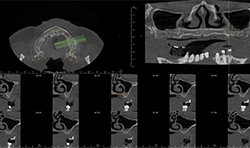

Two-dimensional imaging can’t evaluate the volume of the alveolar process accurately, especially in the buccolingual direction (Fig. 3)

CBCT imaging shows the volume of the alveolar process in any direction for implant treatment planning. (Figs. 4A, 4B) CBCT software allows one to measure the height and width of the alveolar ridge (Fig. 4C). This patient doesn’t have adequate bone volume for implant placement in the posterior left maxilla (Fig. 4D). Due to the severe alveolar ridge resorption, gaining adequate bone volume was recommended.